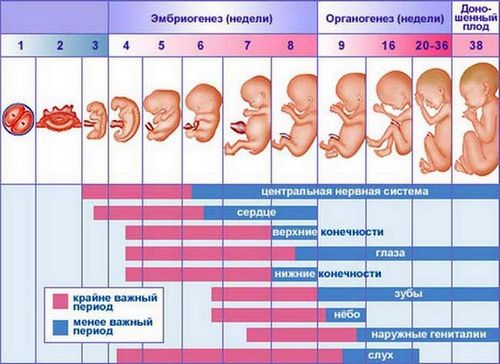

Називати на цьому етапі клітку плодом не зовсім коректно, оскільки до закладки органів прийнято вважати його ембріоном. Як виглядає майбутній малюк зараз? Коли термін вагітності 2-3 тижні, розмір плода ледве сягає пари міліметрів, а сам він по суті є всього лише скупченням клітин, з яких через швидке час почнуть формуватися органи і системи. Але початок вже покладено, і незабаром цей крихітний ембріончік стане найріднішим чоловічком.